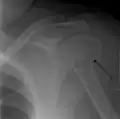

A fracture of the greater tuberosity as seen on AP X ray

A fracture of the greater tuberosity of the humerus